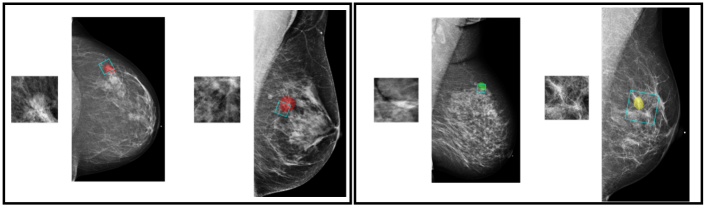

To extract information from image patches, we train a deep convolutional neural network (DCNN) to classify image patches of 256256 pixels as one of the four classes: “malignant”, “benign”, “outside” and “negative.” Malignant and benign patches are cropped from windows that overlap with the segmentation of a malignant lesion or benign tissue. Besides cropping image patches that overlap with the annotations, we sample patches that have no overlap with any lesion (“outside”), as well as patches from breasts without records of biopsy (“negative”). The inclusion of these additional data is intended to regularize the model similarly to data augmentation. Examples of patches from each class are shown in Figure 3.

![]() |

|

| a | b |

| c | d |